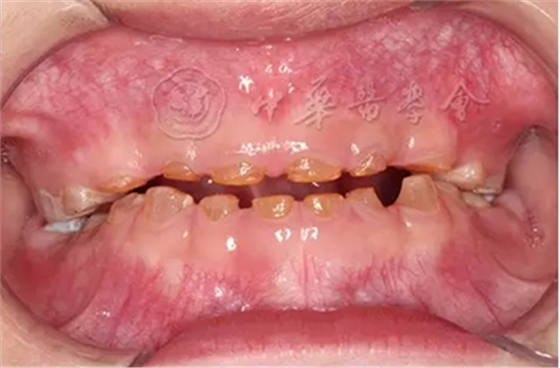

(1)疾病定義及口腔表現(xiàn):成骨不全是一種少見的先天性骨骼發(fā)育障礙性疾病,是由于Ⅰ型膠原ɑ1鏈編碼基因COL1A1和ɑ2鏈編碼基因COL1A2突變導致的結締組織遺傳性疾病,遺傳方式為常染色體顯性或隱性遺傳。成骨不全的臨床主要特征為多發(fā)性骨折、關節(jié)松弛、藍鞏膜、牙本質發(fā)育不全和進行性耳聾。根據(jù)疾病的臨床表現(xiàn)和遺傳方式分為4型,其中Ⅰ型和Ⅳ型有牙齒的表現(xiàn)。患兒乳牙和恒牙呈琥珀色或藍灰色半透明狀,釉質正?;虬l(fā)育不全、易剝脫,牙齒磨耗明顯(圖4)。患者全口牙齒磨損嚴重,面下1/3垂直距離降低。影像學檢查顯示牙齒冠根交界處變窄,早期牙髓腔寬大,隨著牙齒的不斷磨耗,大量繼發(fā)性牙本質沉積,髓腔明顯縮小甚至閉鎖,根管呈細線狀,嚴重時完全消失。組織病理學檢查可見釉質牙本質界變平,缺少正常貝殼狀結構。牙本質結構異常,牙本質小管數(shù)目減少、排列紊亂。

圖4 5歲成骨不全癥患兒乳牙呈琥鉑色,重度磨耗